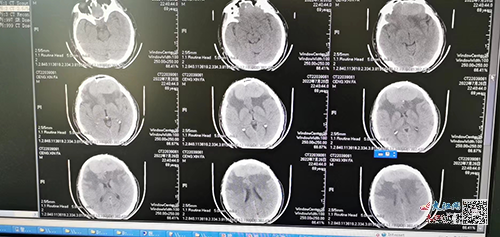

患者矢狀竇旁腦膜瘤術(shù)后5年出現(xiàn)言語遲緩,反應(yīng)遲鈍,肢體活動減少。經(jīng)CT檢查診斷為腫瘤復(fù)發(fā)且為雙側(cè)竇旁腦膜瘤。該腫瘤有網(wǎng)球狀大小,周圍有大量的血管,矢狀竇、雙側(cè)大腦前動脈及各引流靜脈都和腫瘤關(guān)系密切,盤根錯節(jié),手術(shù)稍有不慎就會引起嚴(yán)重的并發(fā)癥。

術(shù)前,神經(jīng)外科團(tuán)隊(duì)充分進(jìn)行討論,制定詳細(xì)的手術(shù)方案,并利用該院鐘世鎮(zhèn)院士工作站3D打印技術(shù),通過3D建模并打印同比例腫瘤及周圍顱骨、血管等模型。通過等比例的3D打印模型,直觀地掌握患者腦腫瘤的體表定位、腫瘤和血管的關(guān)系、矢狀竇閉塞的情況。同時,利用該模型反復(fù)進(jìn)行模擬手術(shù),制定最佳的體位、手術(shù)路徑和方案,并做好各個細(xì)節(jié)處理的詳盡計(jì)劃。

前期的精心準(zhǔn)備確保了手術(shù)的順暢進(jìn)行,在開顱后醫(yī)院曾瑞亮主任醫(yī)師在顯微鏡下按照術(shù)前的預(yù)定方案精細(xì)操作,一個半小時完整切除腫瘤。通過3D打印技術(shù)的精準(zhǔn)定位,術(shù)中對腫瘤周圍每根血管的處理做到了心中有數(shù),有效縮短了手術(shù)時間,出血量明顯減少。術(shù)中腦組織和血管得到了良好的保護(hù),術(shù)后3天患者就可以下床活動。